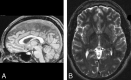

Materials and methods: Brain MR images of 100 healthy young volunteers were randomly selected from our International Consortium for Brain Mapping project data base. Cysts were detected as circular areas of isointensity relative to CSF on both 3D gradient-echo T1-weighted and 2D fast spin-echo T2-weighted images. The inner diameters of all visualized pineal cysts were measured, and a criterion of 2.0 mm of the largest inner cross-sectional diameter was used to categorize cysts as being either small cystic changes (<2.0-mm diameter) or pineal cysts (>2.0-mm diameter).

Results: Twenty-three percent (23/100) of the volunteers had pineal cysts with a mean largest inner cross-sectional diameter of 4.3 mm (range, 2-14 mm); 13% (13/100) demonstrated cystic changes involving the pineal gland with the largest inner cross-sectional diameter of less than 2.0 mm. There was a slight female predominance. Two subjects with long-term follow-up scans showed no symptoms or changes in the size of their pineal cysts.

Conclusion: On high-resolution MR imaging, the prevalence of pineal cysts was 23% in our healthy group of adults, which is consistent with previous autopsy studies. Long-term follow-up studies of 2 cases demonstrated the stability of the cysts.